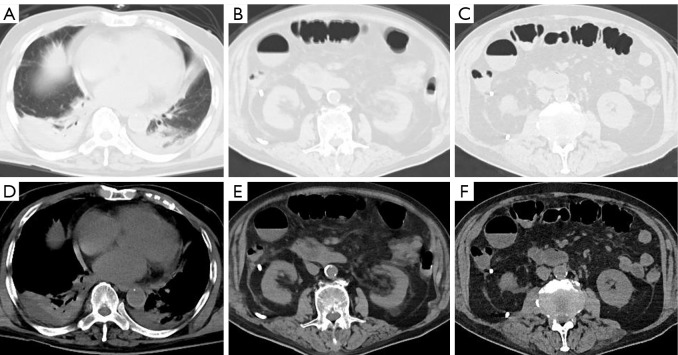

Case description: This retrospective study reviewed seven cases showing duodenal perforation after ERCP for choledocholithiasis between 2019 and 2024. The patients showed clinical symptoms such as fever, abdominal pain, and abdominal distension within 1-3 days after ERCP, and were managed with the interventional three-tube method (insertion of a nasointestinal feeding tube for enteral nutrition, a gastrointestinal decompression tube, and a percutaneous drainage tube for drainage of pus and air). After 5-7 days of hospitalization, the patients were discharged upon stabilization. All patients showed successful healing of duodenal perforation during follow-up.